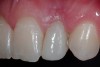

A 19-year-old non-smoking female presented for tooth replacement at the maxillary right and left lateral incisors, which were congenitally missing (Figure 1). The post-orthodontic result was adequate for the placement of 3-mm one-piece small-diameter implants. The preoperative radiographs can be seen in Figure 2 and Figure 3. The pretreatment clinical view in Figure 4 and Figure 5 shows the small intertooth space present in the lateral incisor areas. One of the most challenging tasks with congenitally missing lateral incisor cases is to create an acceptable soft tissue emergence profile from a crestal profile that is flat from the mesial of the canines to the distal of the centrals (Figure 4 and Figure 5). After pretreatment planning which consisted of a complete medical and dental history, radiographic analysis, and upper and lower study models mounted by a facebow transfer technique, the fabrication of a TempStent II surgical guide was completed. Figure 6 and Figure 7 show the occlusal view of the TempStent II guide on the study cast and in the oral cavity, respectively.

Figure 1  Pretreatment clinical view.

Figure 1

Figure 4  Pretreatment clinical view, right lateral incisor.

Figure 4

Figure 5  Pretreatment clinical view, left lateral incisor.

Figure 5